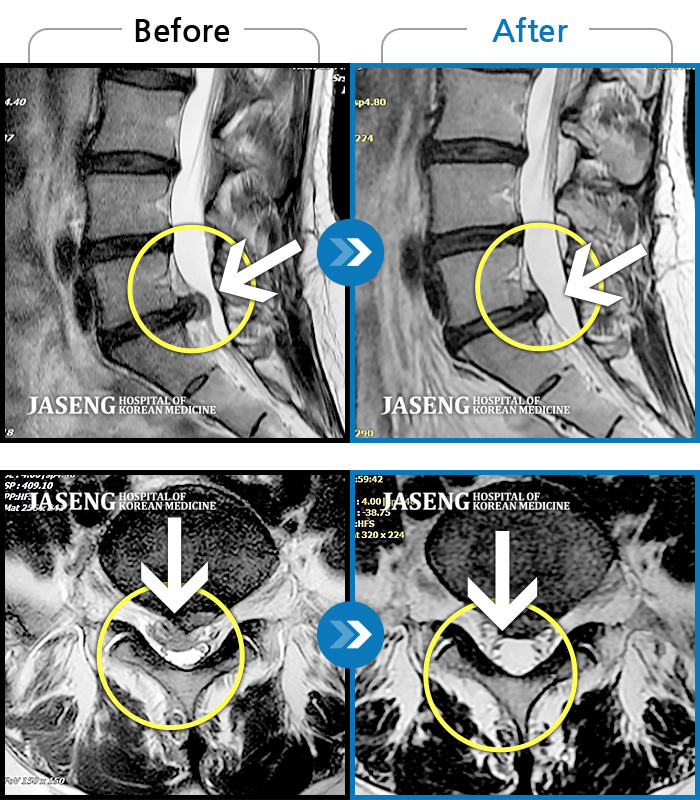

Before

After

환자에게 사전 동의를 받아 동일 조건에서 촬영되었습니다.

개인에 따라 치료 후 부작용이 발생할 수 있으니 의료진과 상담 후 치료를 진행하시기 바랍니다.

좌측 허리와 골반 통증, 좌측 다리에 통증과 저림

허리디스크로 연골이 거의 없다고 진단 받음